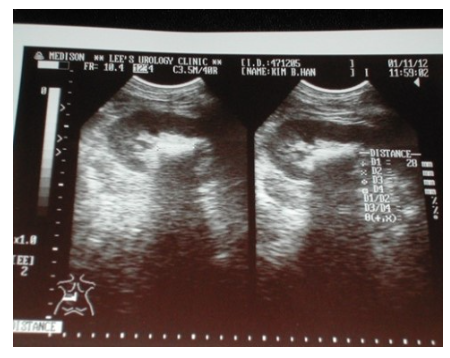

3) 체외충격파쇄석술

체외충격파쇄석술은 수술 조작 없이 몸 밖에서 충격파를 발사하여 결석을 잘게 분쇄하여 자연 배출이 되도록 유도하는 치료법으로 쇄석술 후에 분쇄된 결석은 대개 2주 이내에 자연적으로 배출되며 3개월 후 시술의 성공 여부를 판정하게 됩니다.